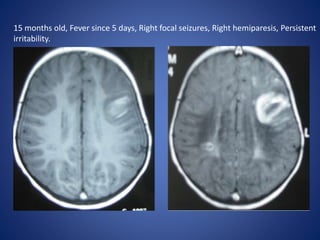

15 months old, Fever since 5 days, Right focal seizures, Right hemiparesis, Persistent

irritability.

15 months old,Fever since 5 days, Right focal seizures, Right hemiparesis, Persistent irritability.

The classic features that indicate CSVT include the

• “Dense triangle” or the “Cord sign,” which describe the

increased density over the thrombosed venous sinus in a plain

CT,

• “Empty triangle” or “Empty delta (δ) ” sign in a contrast-

enhanced CT.

DWI is a sensitive technique for detecting areas of infarction.

Parenchymal changes can be seen within minutes of injury, which

allows for early identification and intervention